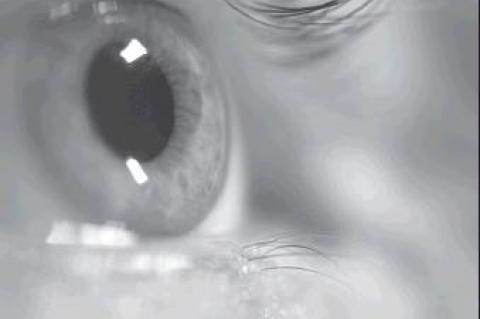

Don’t Get Caught Off Guard By Glaucoma Posted in: News Vision should never be taken for granted. Appreciating one’s sense ...PLEASE LOG IN FOR PREMIUM CONTENT. Our website requires visitors to log in to view the best local news. Not yet a subscriber? Subscribe today!